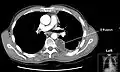

Chest computed tomography is more accurate for diagnosis and may be obtained to better characterize the presence, size, and characteristics of a pleural effusion. Lung ultrasound, nearly as accurate as CT and more accurate than chest X-ray, is increasingly being used at the point of care to diagnose pleural effusions, with the advantage that it is a safe, dynamic, and repeatable imaging modality.[18] To increase diagnostic accuracy of detection of pleural effusion sonographically, markers such as boomerang and VIP signs can be utilized.[19]